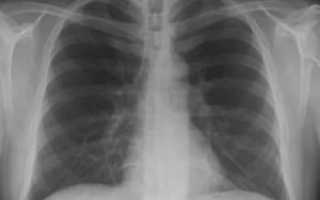

Своевременная диагностика пневмонии (воспаления легких) играет важную роль в проведении комплексного обследования и назначении правильного лечения. Главным диагностическим методом является рентгенологическое исследование легких.

Поэтому пневмония на рентгене становится решающим фактором при выборе тактики лечения.

Пневмония – это заболевание, характеризующееся поражением нижних дыхательных путей. Рентгенография назначается при выявлении клинической картины воспаления легких. В отличие от других методов рентгеновское обследование считается самым доступным.

Часто пациенты, которых направляют на обследование, задаются вопросом, покажет ли рентген пневмонию. Да. С помощью такой процедуры на снимке можно увидеть воспаленные участки, оценить состояние легочного рисунка и корней легких.

Расшифровка пневмонии на рентгеновских снимках проводится по четырем признакам: изменение рисунка и корней легкого, затемнения и просветления. Признакам, указывающим на пневмонию, которые можно увидеть на снимках, свидетельствуют такие критерии:

Однозначные признаки пневмонии на рентгене – это затемнения какого-то участка легочного поля.

Выявляются очаговые тени либо распространенное, сливное снижение прозрачности. Характерны нечеткие размытые контуры.